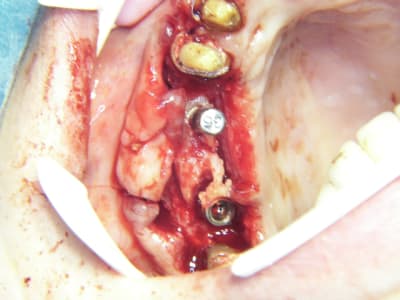

bon et bien ça c'est fait!

curetage (deux bonnes heures) dépose des deux vis d'ostéo et de l'implant en 16, nettoyage implant en 14/15 (axe un peu limite pour cause structure osseuse) et 17.

Vitalos

le greffon placé il y a 6 mois (grosse corticale) était dans le "vide" au niveau de 14, et il m'aurait fallu le piezzo éventuellement (il n'était pas installé, pour cette chir) pour "percer" la corticale sans pression, car à la fraise, je sentais le bloc plier, et nous avons préférés (avec le confrère) tenter un compromis pour la prothèse qui ne sera pas catastrophique et devrait permettre à la patient (qui a déjà subie 2 greffes, menton et ramique, avec un souvenir sympa du menton d'ailleurs)d'avoir une reconstruction fixe.

je ne sais pas si le vitalos permettra de rattraper ce cas là, mais vu tous les soucis que nous avons rencontrés pour le nettoyage (biooss infiltré dans la muqueuse de partout, j'ai du "virer" 60% du périoste et honnêtement je ne savais pas trop comment faire un "abri" de reconstruction pour l'os et l"environnement tissulaire, de façon simple.

j'avoue que j'ai une préférence, (pas encore une addiction mais presque) pour le vitalos, ou tout produit facile à appliquer, avec des précautions bien sur, et dont les résultats sont prédictibles, si il n'y a pas d'erreur à la pose, et que lors des sutures il n'y a pas de "chocs" parasitant la prise du matériaux.

photos montrant le hiatus greffe/os et pose avec vitalos à la fin